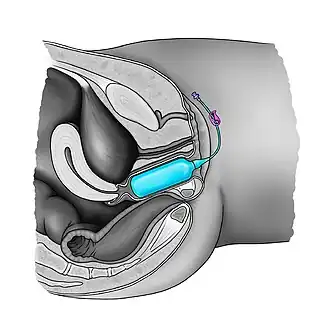

Balloon vaginoplasty

In this procedure, a Foley catheter is laparoscopically inserted to the rectouterine pouch whereupon gradual traction and distension are applied to create a neovagina.